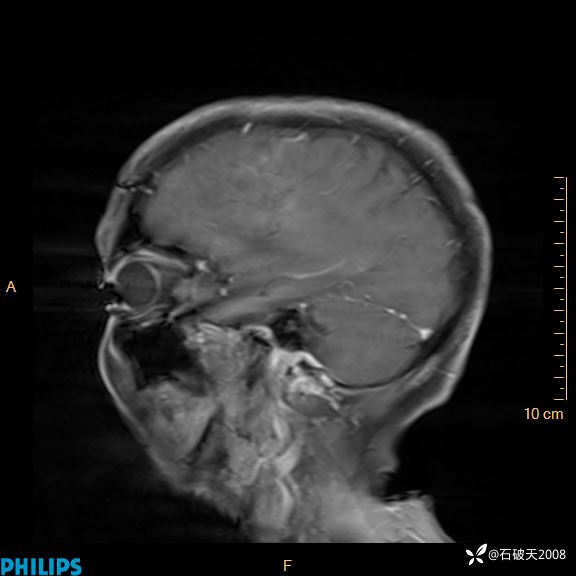

2024.2.21MR

增强矢状位